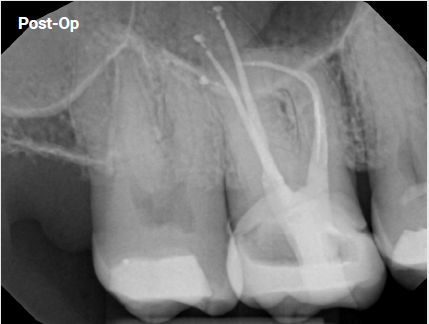

The patient came in with discomfort on tooth #19

The Case: The patient came in with discomfort on tooth #19. The diagnosis was a necrotic pulp with acute apical periodontitis…